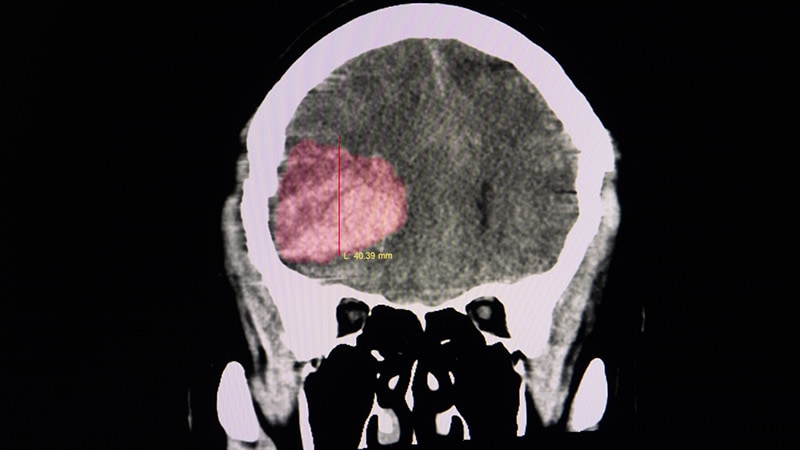

WSC 2023Oral Anticoagulation in ICH Patients With AF: New DataNew information has become available to help guide clinicians on the thorny issue of whether to give oral anticoagulation to patients with AF who have had an intracranial hemorrhage.